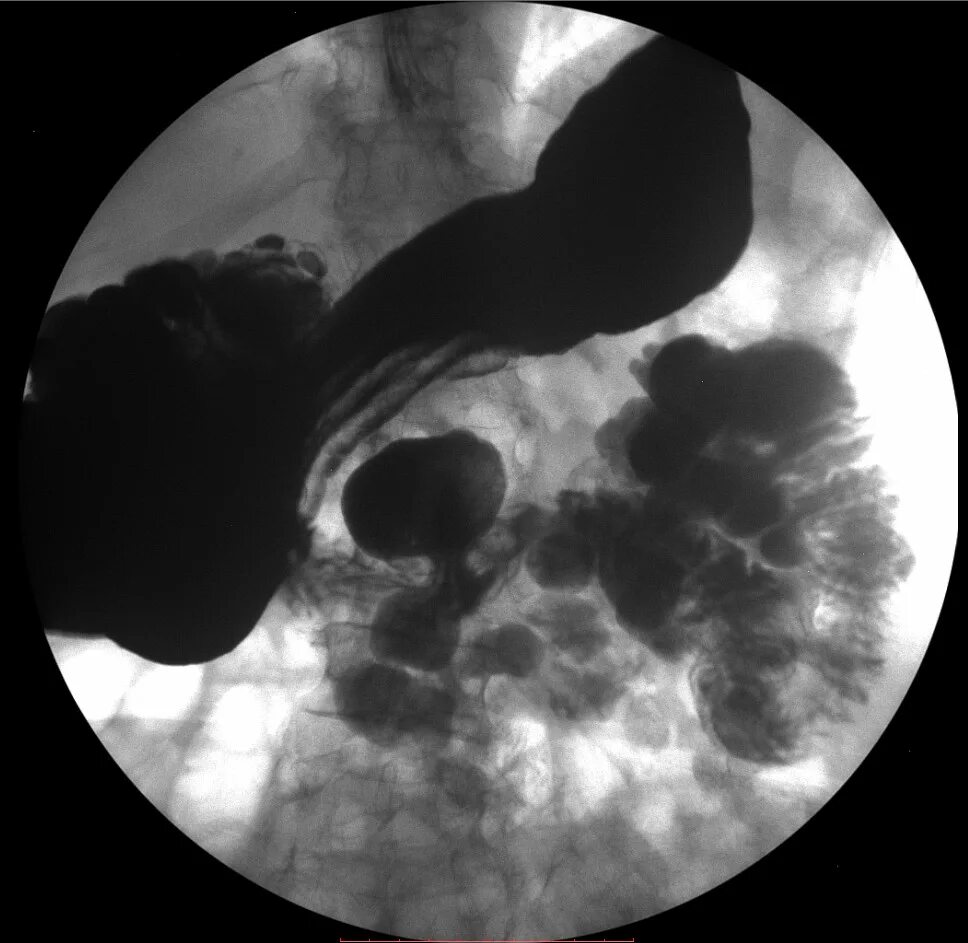

Дивертикул трахеи